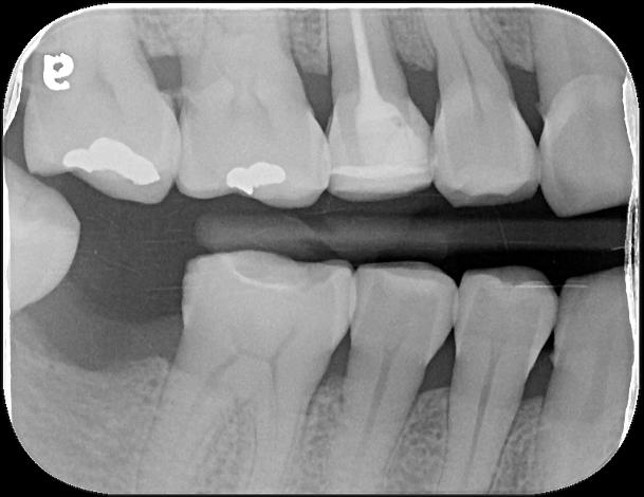

根尖照,邊緣完整